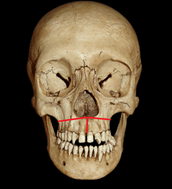

3. Consolidation phase: Phase where the bone dimension is the desired one and it is finished mineralizing (Figure 1 & 2).5

Figure 1 Image of a Le Fort 1 osteotomy line is inserted with its modification by performing an osteotomy in the intermaxillary suture.

Figure 2 Image showing the osteotomy line in the intermaxillary suture to create disjunction of the palate.